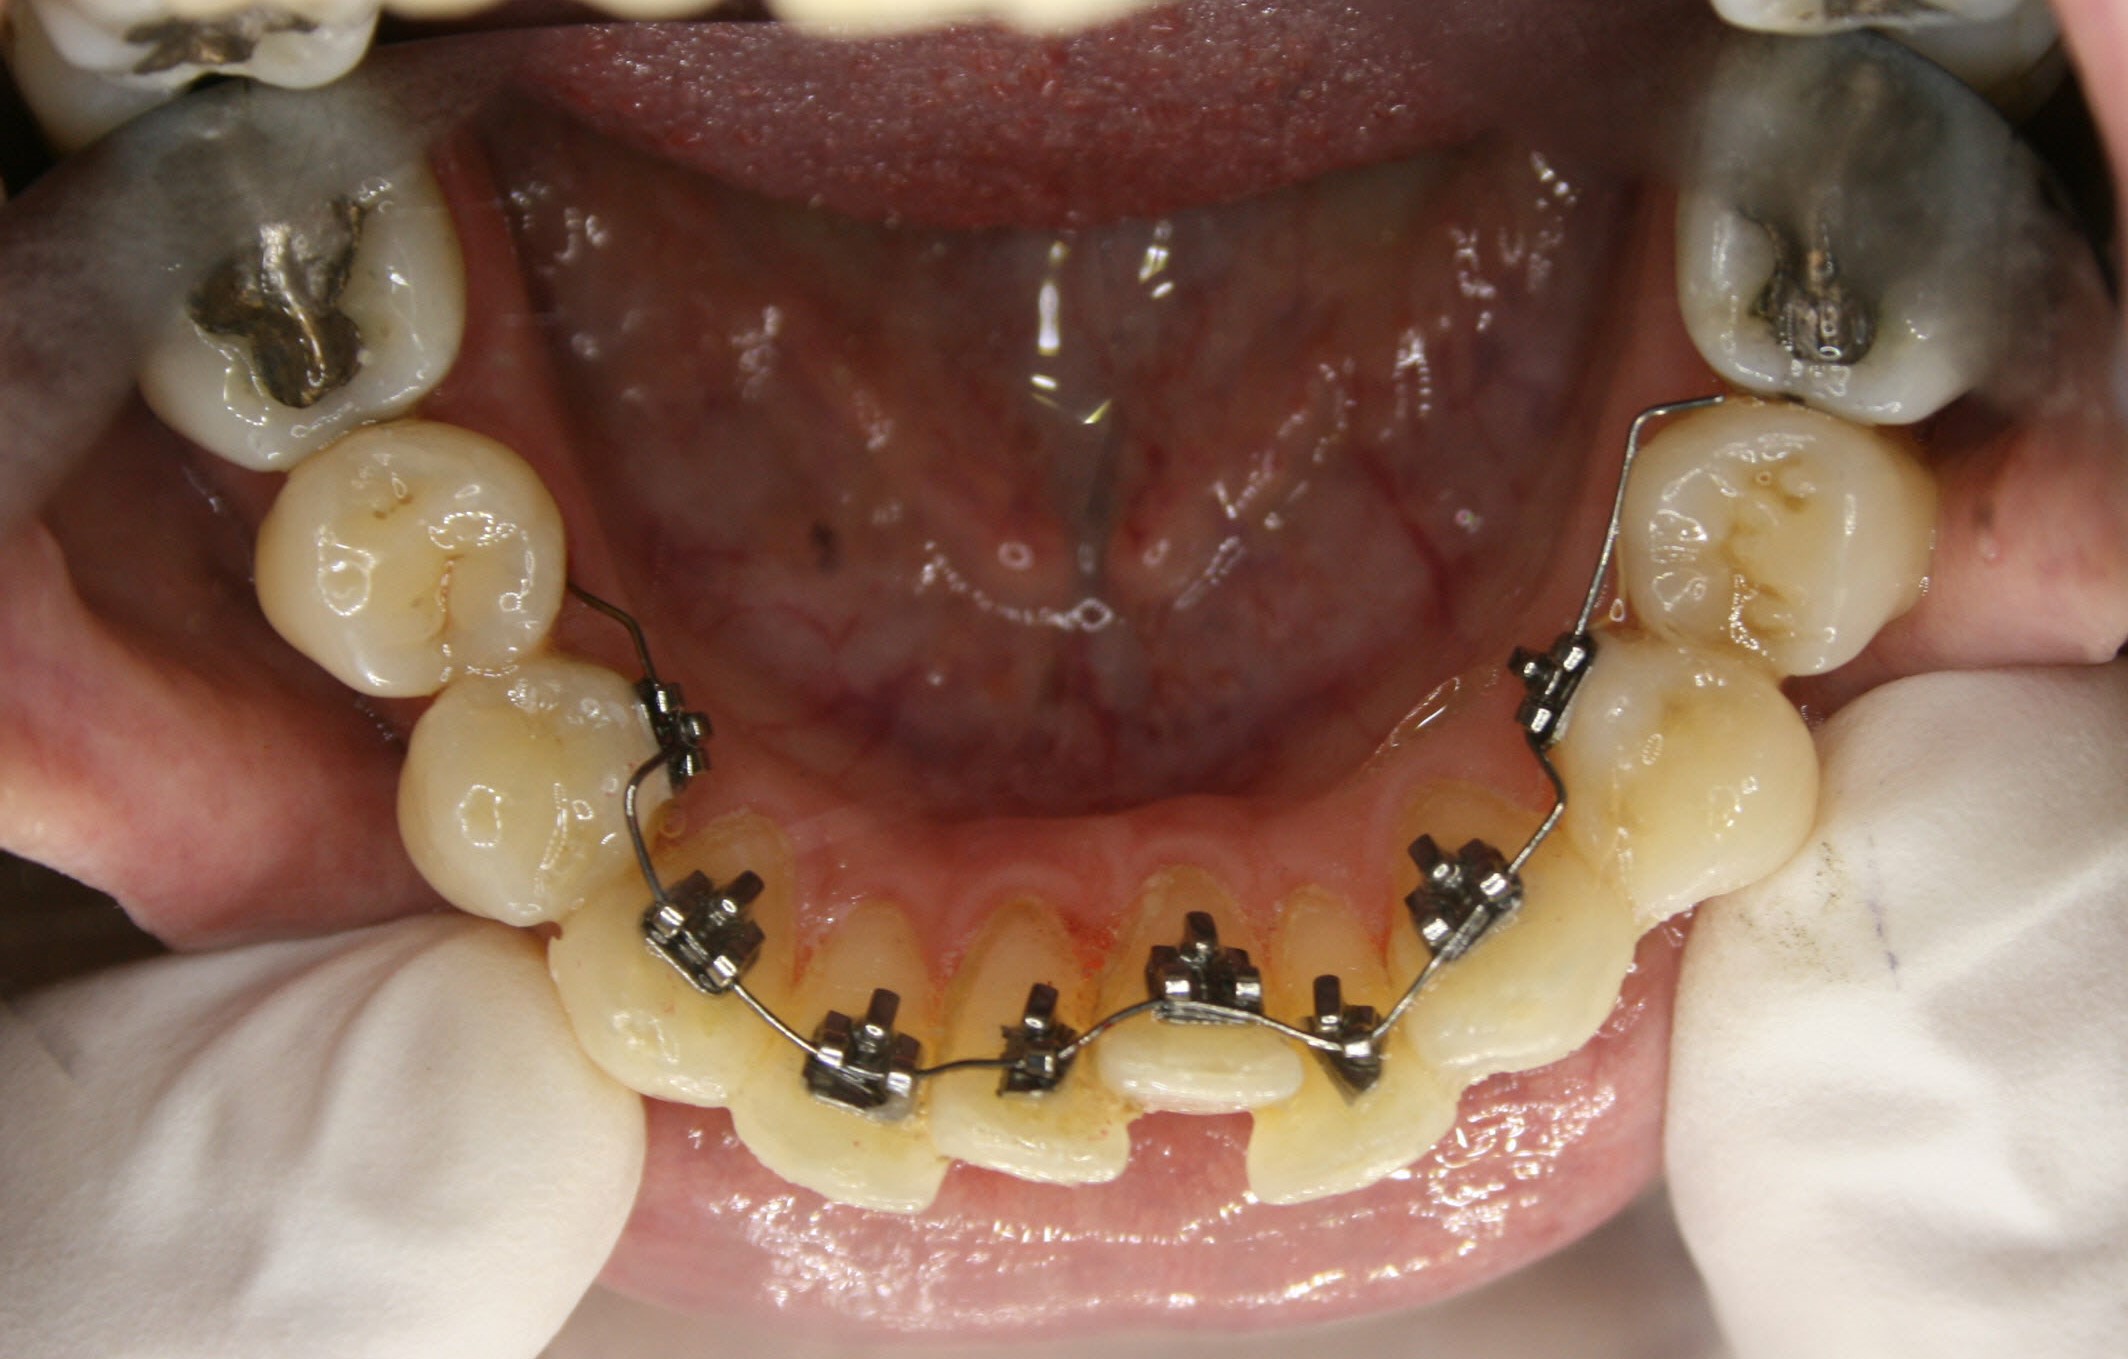

Im Unterkiefer kam auch eine auf der Innenseite der Zähne befestigte Zahnspange zum Einsatz; da es keine Lückenschlußaufgabe zu bewältigen gab, konnte ein einfacheres System verwendet werden. Es ist angenehmer für die Zunge, weil es flacher ist als das aufwendigere System im Oberkiefer. Siehe hierzu auch die Ausführungen im Abschnitt „Behandlungsmethoden – Welche Arten von Zahnspangen gibt es". Die Ausformung des Unterkiefers war nach einem Jahr und 2 Monaten abgeschlossen.